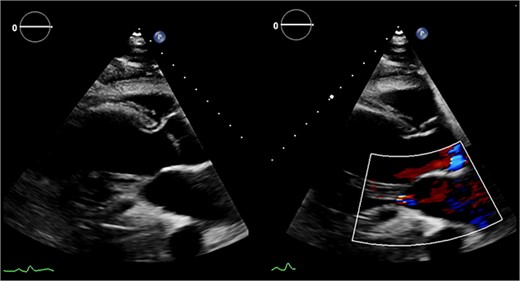

The heart was deaired and pacing wires placed. Despite successful initial weaning from cardiopulmonary bypass (CPB) with support (dopamine, adrenaline, noradrenaline), repeat pharmacological intervention was necessary. Central veno-arterial extracorporeal membrane oxygenation (VA-ECMO) was established by exchanging bicaval cannulae for a two-stage venous drainage cannula and utilizing the existing aortic cannula. Flows of 4–5 L/min were maintained, and the heart continued to eject with aortic valve opening. The patient was transferred to intensive care in a stable condition and recovered on ECMO for 6 days before decannulation and chest closure 48 h later. Following medical optimisation, he was discharged on postoperative day sixteen. Postoperative echocardiography (Fig. 6) revealed LV improvement (LVEF 45%) with a competent MV (trace regurgitation, no stenosis). At 1-year follow-up, the patient was recovering well without complications with preserved ejection fraction and mild residual MR.

Postoperative echocardiography: restoration of mitral valve leaflet coaptation and LV geometry, resulting in trivial regurgitant jet.